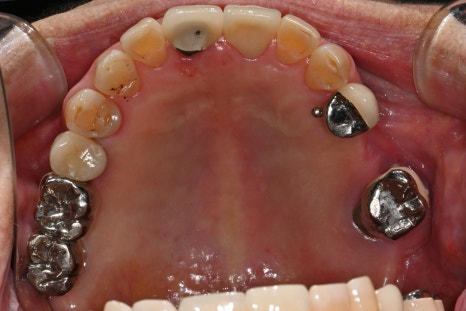

✅ Photos before treatment

Left photo: This panoramic X-ray was taken at the patient’s first visit.

Several molars around the existing implants showed inflammation and mobility, and overall there was reduced chewing function and aesthetic discomfort.

Right photo: An intraoral photo of the patient’s front teeth.

The front teeth were broken and there were also old prosthetics, so both esthetics and function needed to be restored.